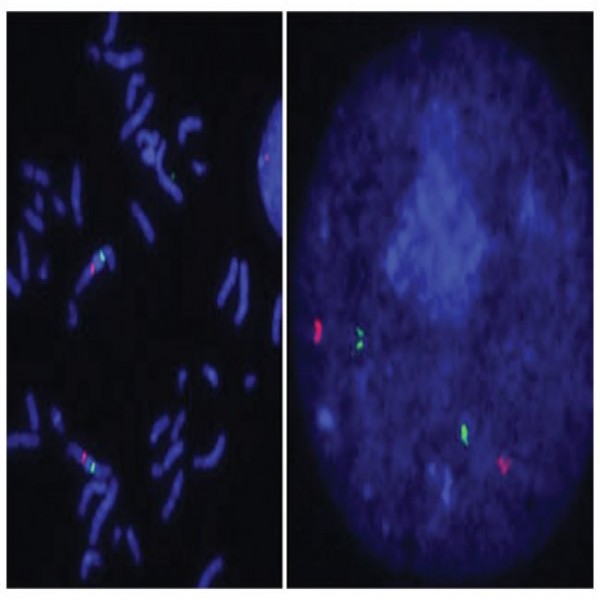

Abnova™ SMO/CEN7q (Texas Red/FITC) FISH Probe

₦3,891,600.00

₦3,891,600.00